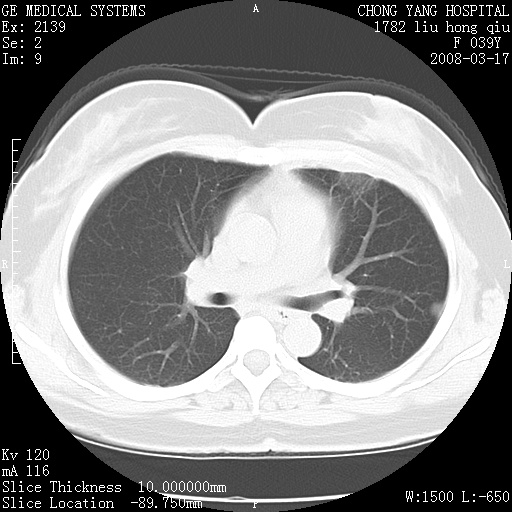

以下是引用yangxue121在2008-5-31 20:24:00的发言:[br]考虑多发胸膜间皮瘤[br]左侧少量胸腔积液[br]肝脏密度不均

以下是引用王仕学在2008-5-31 20:10:00的发言:[br]考虑胸膜间皮瘤。

以下是引用长城干红在2008-5-31 21:42:00的发言:[br]肝脏密度不均,建议增强扫描,胸膜下多发结节,考虑为胸膜来源的原发肿瘤或转移瘤。